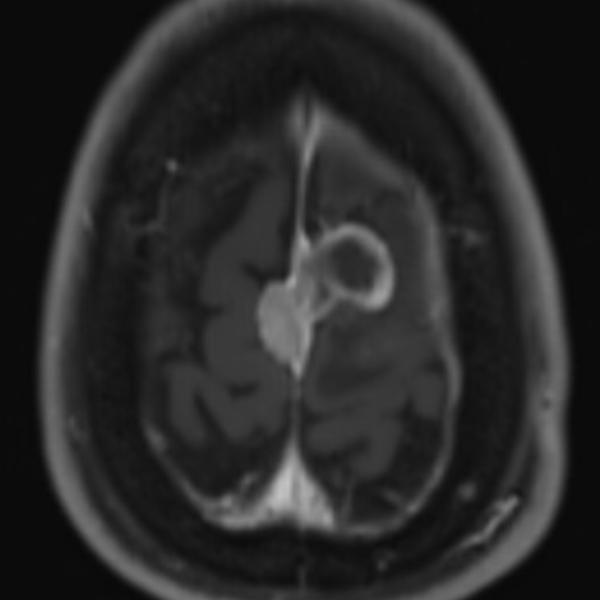

A 52 yo lady has a progression of residual disease after partial resection 5 months ago of a grade II meningioma of the falx. Unfortunately, at that time the patient did not accept treatment.

I would propose irradiating with FSRT the whole cavity and boosting with SRT the macroscopic disease. Would you share this opinion?

If not, and I suspect as much, given 5 months time to progression, then I would take the GTV and the surgical bed plus a 3 mm margin into brain tissue as CTV60/PTV60 (60 Gy in 30) then boost GTV residual +PTV with 6 Gy in 3 frx or 10 Gy in 5 frx depending what your comfortable with. Our data that will be presented and in submission suggests 66 in 33 or 70 Gy in 35 to result in better long term outcomes when residual vs 60 Gy in 30. I do sequential boost but you could SIB also. When volumes of residual are large I SIB otherwise I do the boost sequentially and a week or two gap using the Gamma Knife Icon. I would not single frx boost but fractionate the boost.